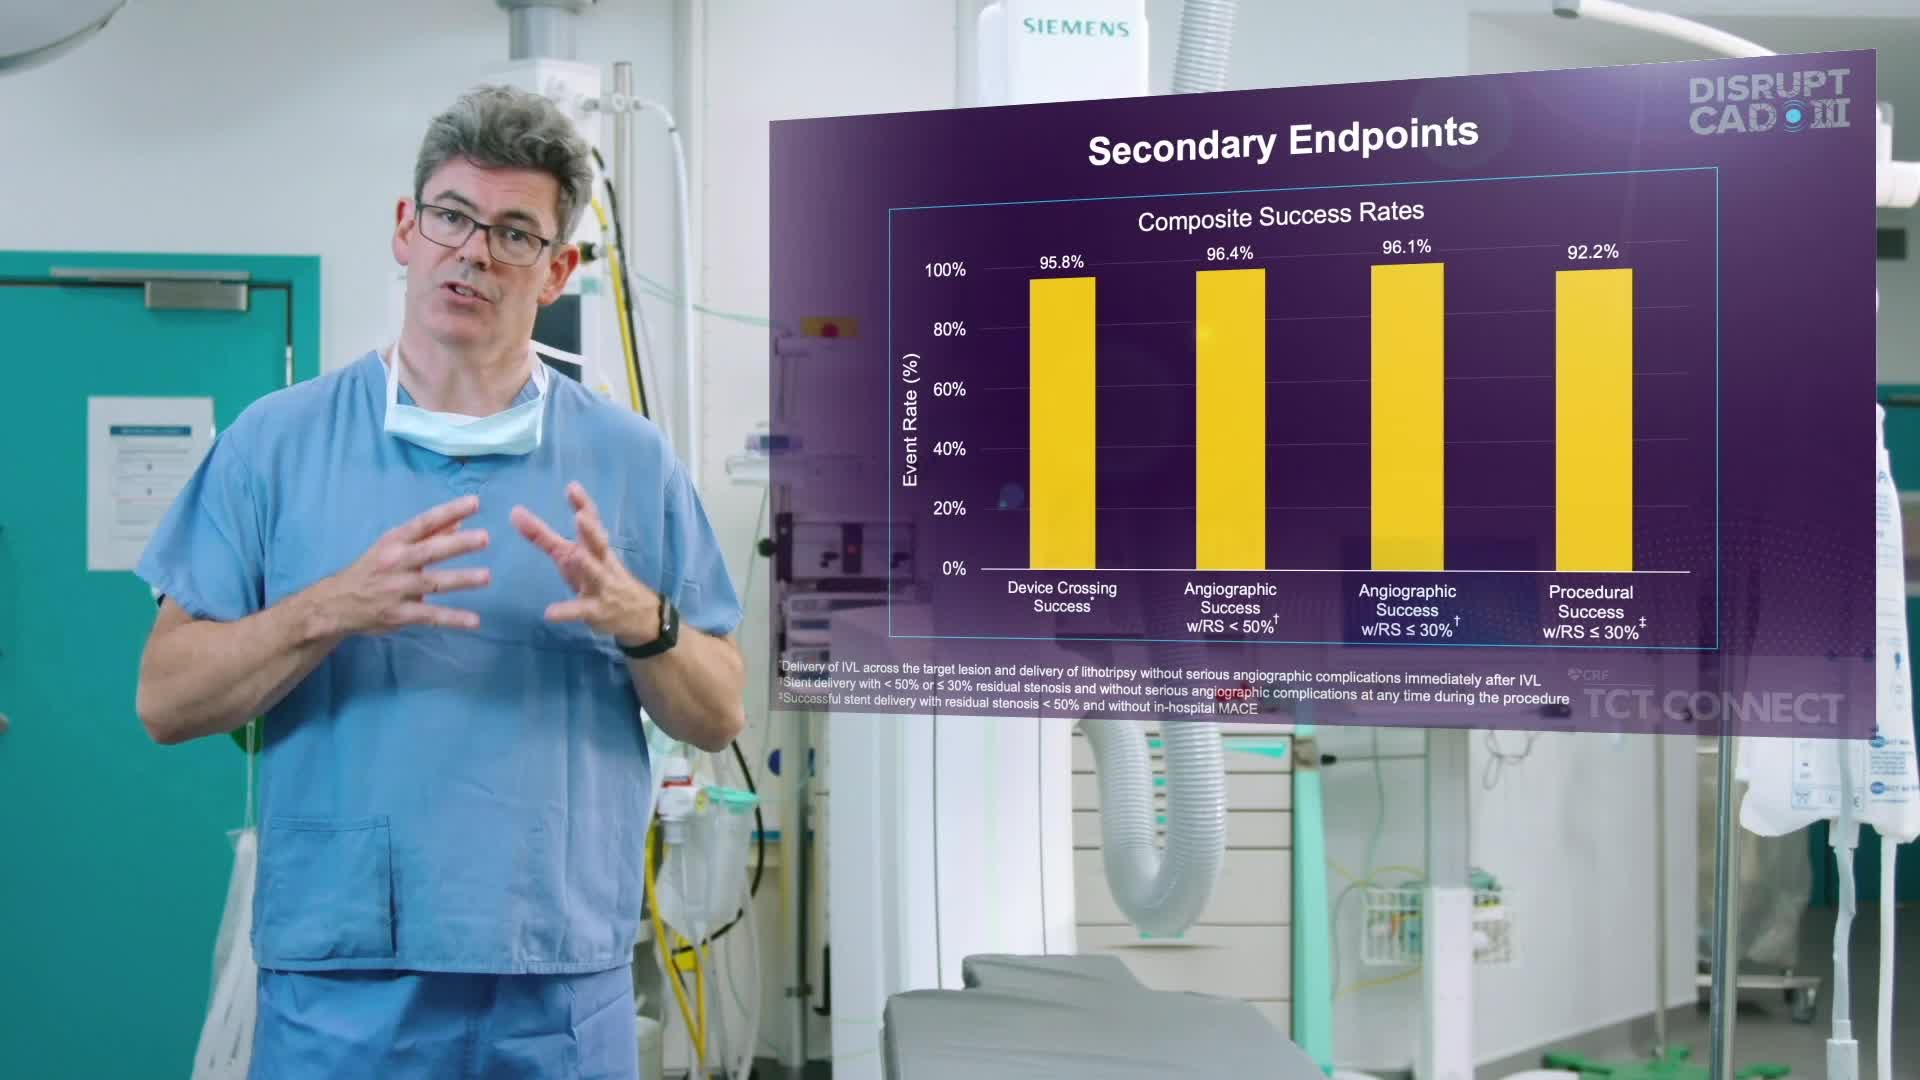

Intravascular Lithotripsy for Treatment of Severely Calcified Coronary Artery Disease: The Disrupt CAD III Study